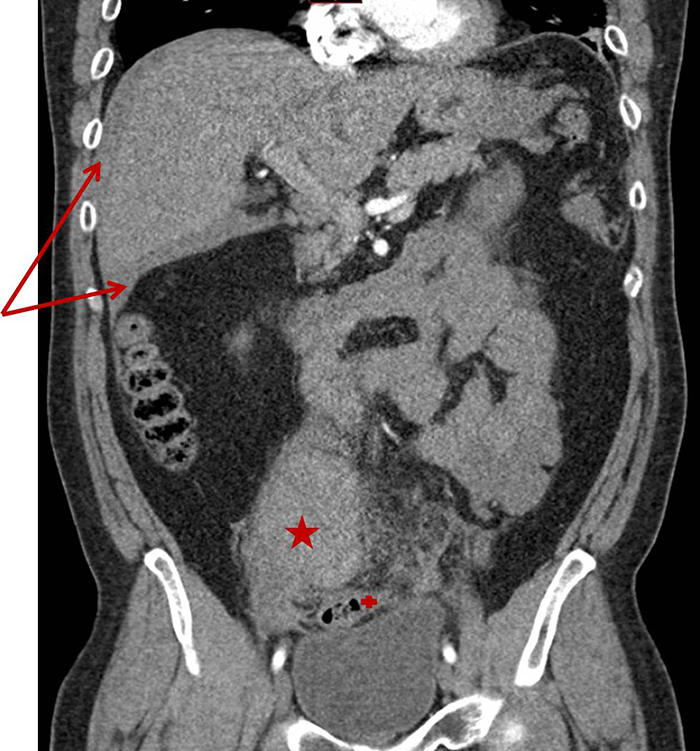

Computed tomography (CT) scan of the abdomen and pelvis revealed diffuse ascites and a 7.4 cm by 7.8 cm fluid collection with a density of 65 Hounsfield units (greater than 50 is consistent with hematoma) within the mid pelvis and right lower quadrant of the abdomen (Figure 1a-b). The mid sigmoid colon was noted to have focal wall thickening with stranding of the surrounding fat (Figure 1).

Figure 1. Figure 1a-b. CT demonstrating hemoperitoneum (arrow) and large clot (*) abutting the sigmoid colon (+).